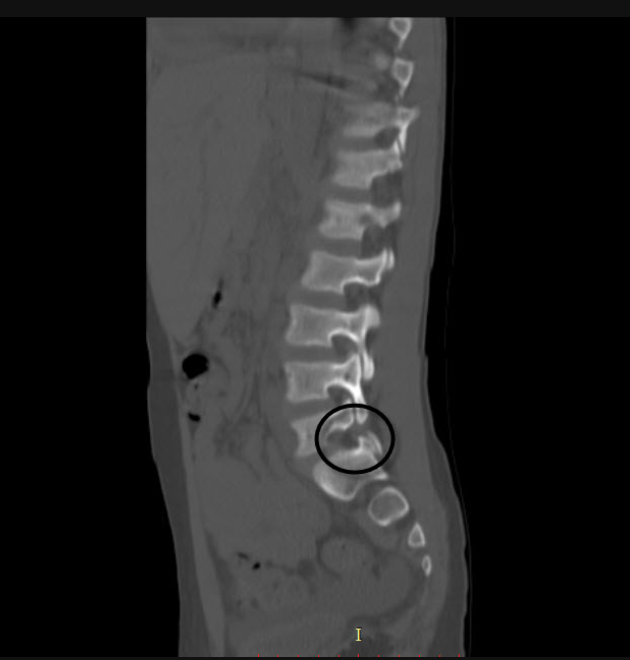

- CT Scan – Gold standard for bony defect visualization

Spondylolysis is a condition characterized by a stress fracture or defect in the pars interarticularis, a small but critical portion of a vertebra. It most commonly affects the lower lumbar spine, especially the L5 vertebra, and is a frequent cause of back pain in adolescents, athletes, and young adults.

Spondylolysis is a defect.